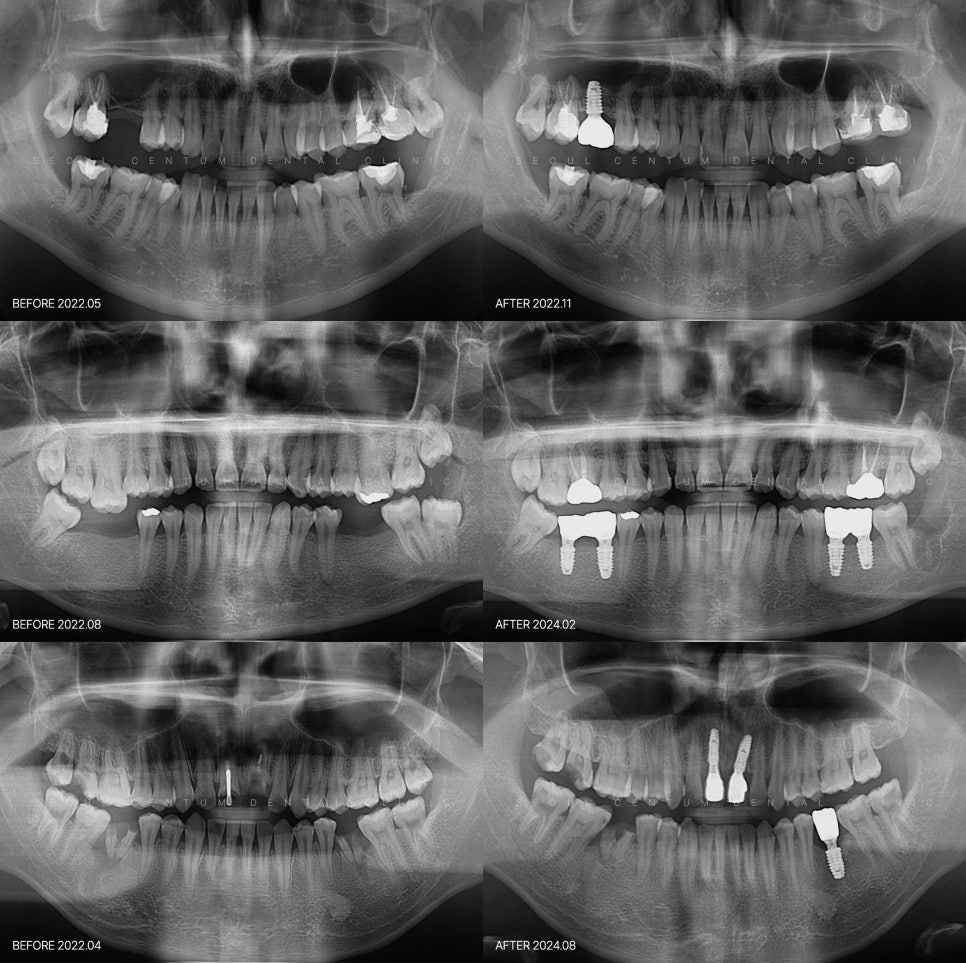

치료의 첫걸음은 기본 개념을 이해하는 일 잇몸에 고정하는 임플란트라는 건 인공치아라는 개념을 넘어 뼈와 잇몸, 보철물까지 복합적으로 얽혀 있는 정교한 구조물이라고 보는 편이 더 정확합니다. 자연치아의 형태, 비율 등의 상당 부분과 유사하게 만들어져 겉으로 봤을 때 이질감이 적은 데다 식립된 후에는 저작 기능을 회복할 수...

서울센텀치과 (신사역)의 네이버 블로그 원문을 보존한 아카이브 페이지입니다. 임플란트 카테고리의 임플란트 구조 하나하나 뜯어보면 알 수 있는 원리 글을 통해 병원의 한국어 정보 제공 방식과 진료 관련 안내 톤을 확인할 수 있습니다.